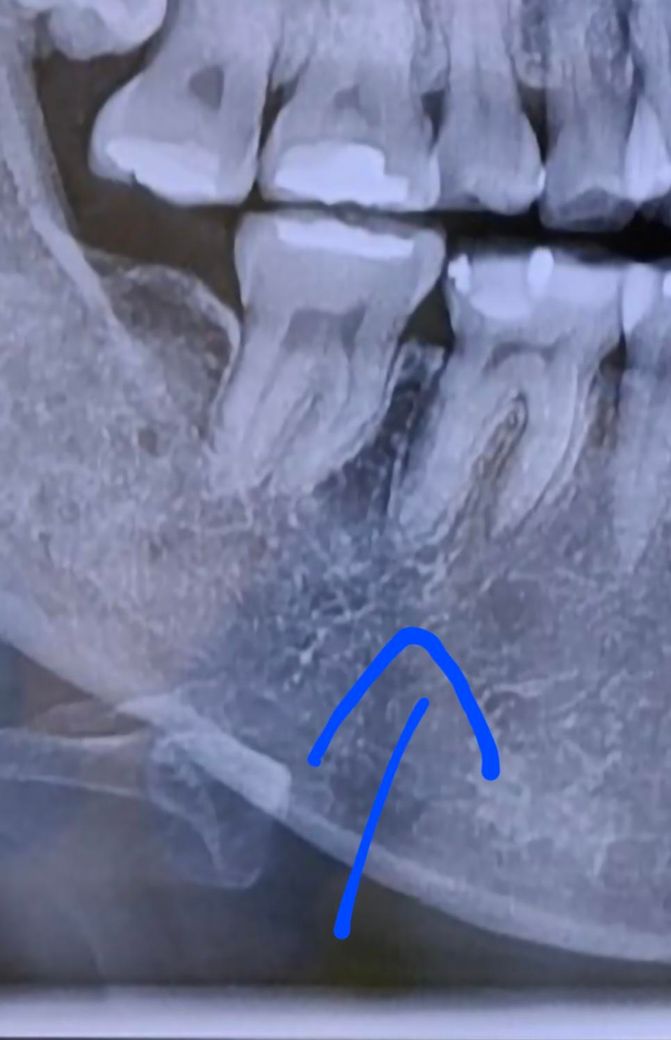

치실이 화살표 표시까지 안아프게 쑥 들어갑니다.

저기만 치실이 많이 들어가는거 같은데

얼마 안된 파노라마 입니다.